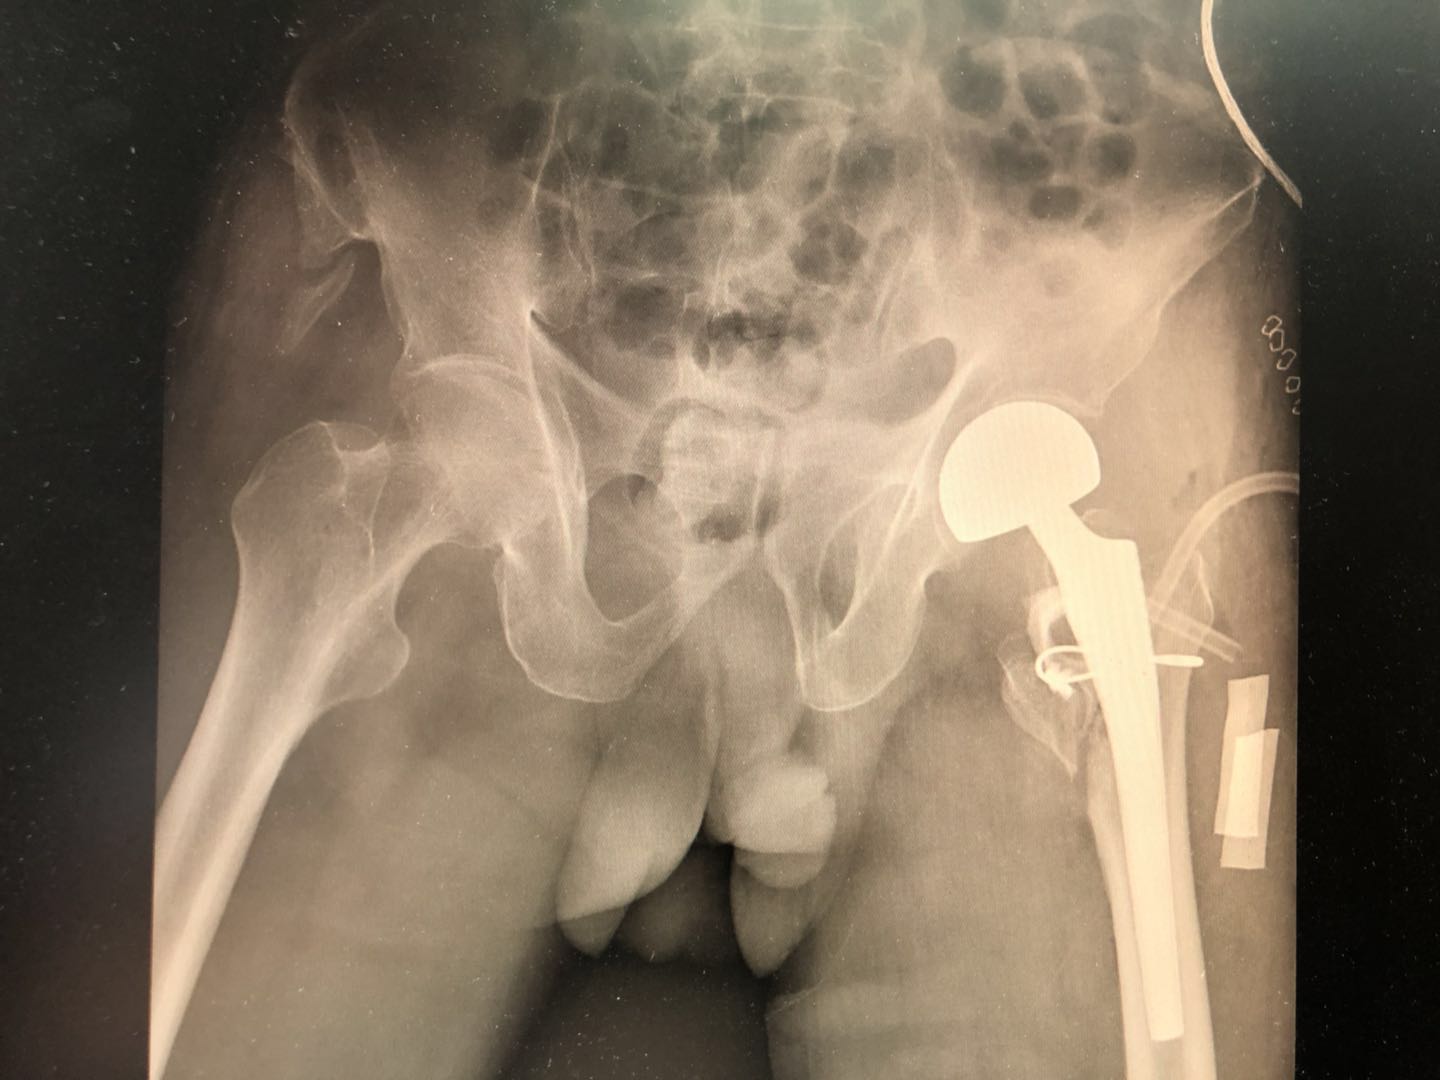

因此,在B医院骨科科室全科讨论后,跟家属交代手术风险后,决定给老人家做关节置换手术!风险是有的,但是不做手术的危害更大!

以下是老人家手术后的效果:

老人家术后3天就可以扶着拐杖,家人陪伴下地走路,手术后1个星期出院回家休养了,肺炎也在慢慢好转!